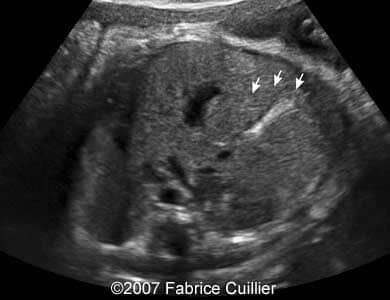

A 30-year-old patient, G3P2, was referred to our clinic at 36 weeks of gestational age after hyperechoic foci were seen in the fetal gallbladder on ultrasound. 13- and 22-week sonographic examinations were unremarkable. The 36-week ultrasound evaluation was normal except for an elongated echogenic mass seen in the gallbladder (Images 1A, 1B, 1C, 1D). Neither ascites nor hydrops were seen. The gallbladder appearance was identical on sonographic re-evaluation at 37 weeks GA (Images 3A, 3B). At 38 weeks of gestational age, a healthy female infant weighing 3200 g was born. There was no evidence of hematologic incompatibility, sepsis, or jaundice. Laboratory values including those for the cystic fibrosis gene, hemoglobinopathy, and liver functions were normal. On the fifth day of life, ultrasound was performed, showing a gallbladder of normal size containing several gallstones (Images 5A, 5B, 5C, 5D).

Images 4A, 4B. Postnatal sonogram showing multiple small echogenic foci in the fetal gallbladder.

5A

5B

Images 4D, 4E. Postnatal sonogram showing multiple small echogenic foci in the fetal gallbladder.

5C

5D